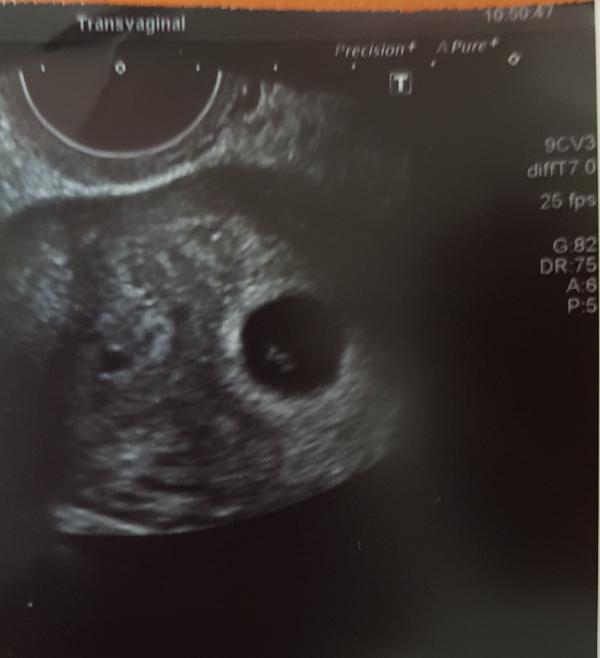

Right so it turns out I have a septate uterus (really long it basically splits it into two) so my consultant wanted to operate on it. Operation will have to wait though as I am 6 weeks 3 days pregnant with a little heartbeat! (Clearly nothing wrong with my fertility!) Anyone on here carried full term with a septate uterus? Or shall I prepare for the worst again?